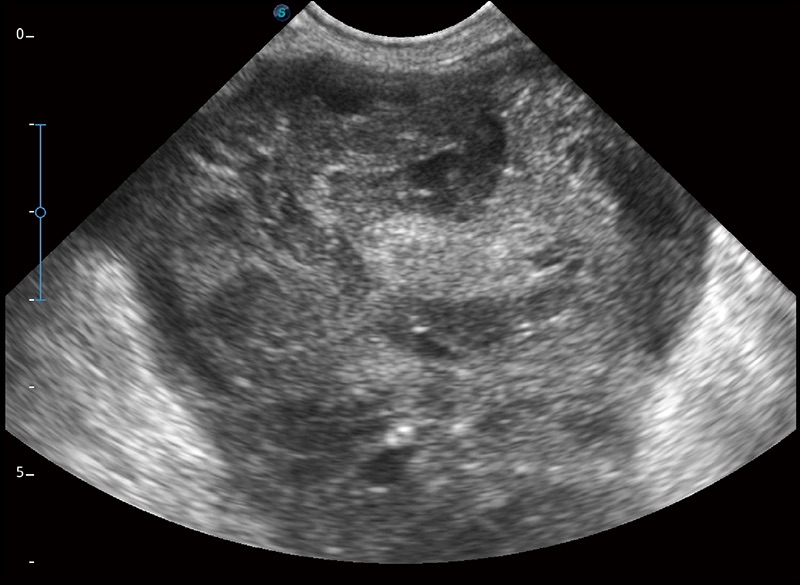

α1卓越的图像质量和便捷的工作流程,使每位宠物医生都能轻松扫查。其全面的兽用应用功能和紧凑型的结构设计,可以满足动物检查的多种需要。专业的预设检查模式和多领域测量软件包有助于为不同类型的动物提供检查, 让宠物医生能够出色的完成工作。

扩展成像

支持线阵和凸阵探头,一键操作即可获得更宽的图像视野

实时宽景成像

可实时观察感兴趣区域和病变位置